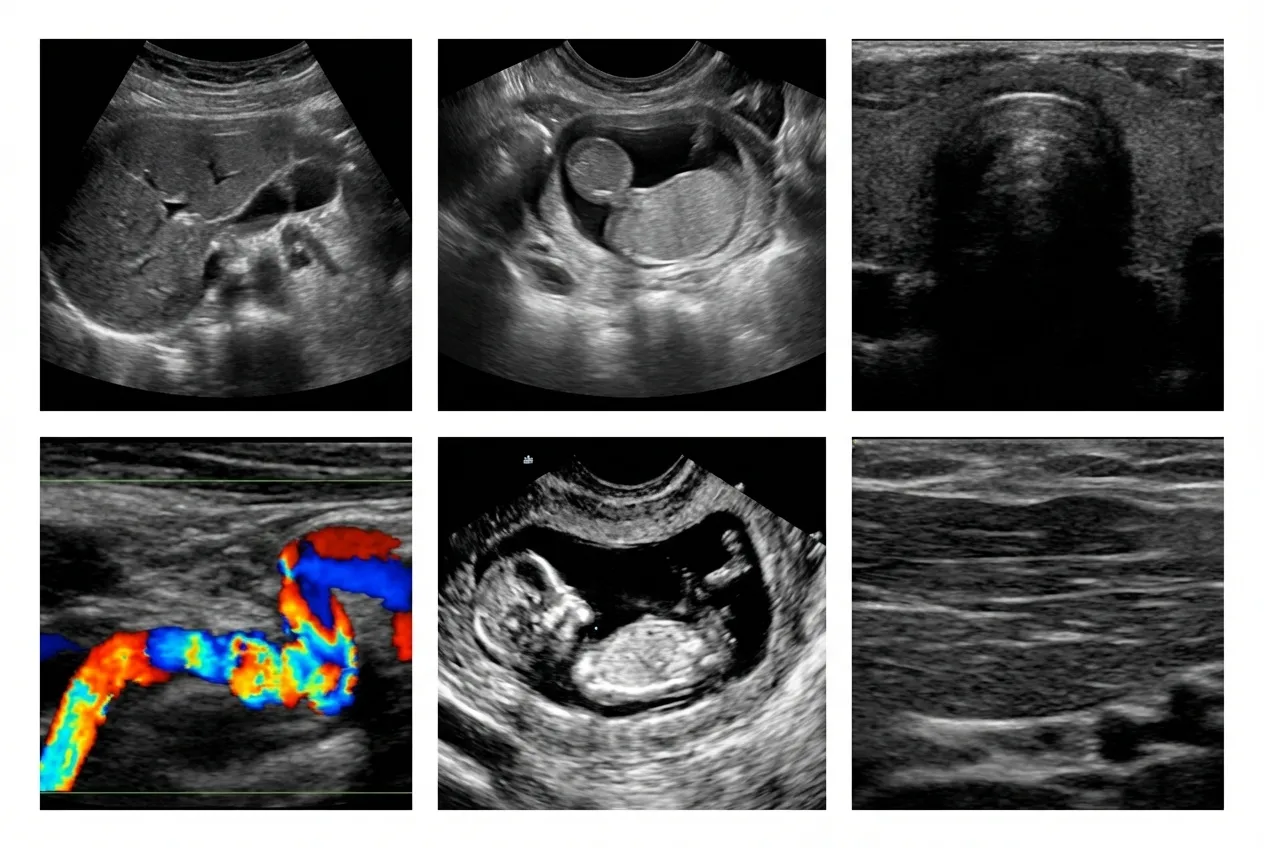

Abdominal Ultrasound

This ultrasound scan evaluates organs such as the liver, kidneys, and gallbladder, helping detect pain causes, infections, and digestive conditions with accurate and reliable imaging results.

Pelvic Ultrasound

Pelvic ultrasound imaging helps assess reproductive organs, bladder conditions, and internal concerns, supporting accurate diagnosis and treatment planning with clear imaging results.

Thyroid Ultrasound

This ultrasound scan examines the thyroid gland to detect nodules, swelling, or abnormalities, helping providers evaluate function and determine the need for further medical care.

Vascular Ultrasound

Vascular ultrasound evaluates blood flow in arteries and veins, helping detect blockages, clots, and circulation issues with precise, non-invasive diagnostic imaging technology.

Pregnancy Ultrasound

Pregnancy ultrasound provides detailed imaging to monitor fetal development, confirm pregnancy stages, and ensure both mother and baby are progressing safely throughout each stage.

Soft Tissue Ultrasound

This ultrasound scan evaluates muscles, tendons, and soft tissues to detect injuries, swelling, or abnormalities, helping guide accurate diagnosis and effective treatment.